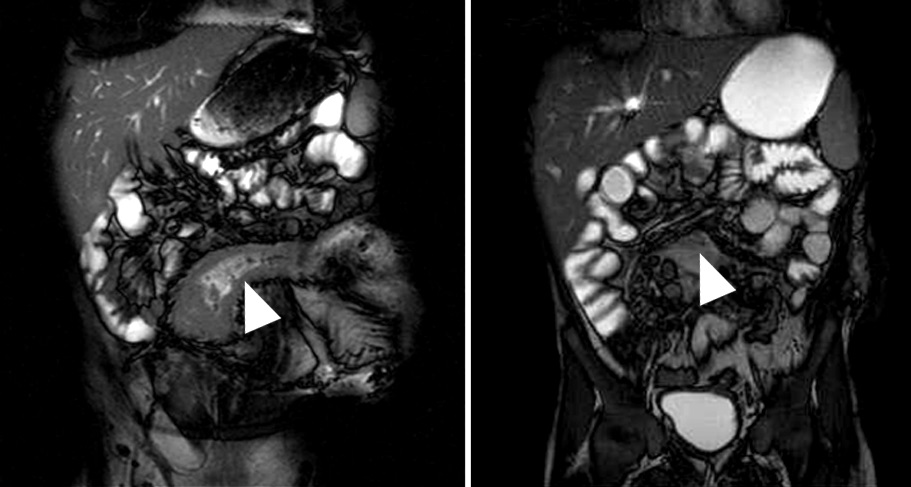

Figura 4

Paciente con enfermedad de Crohn de 10 años de evolución, cursando gestación de 13 semanas. Secuencia eco de gradiente coronal. Asas delgadas de paredes engrosadas en la fosa ilíaca derecha, se idenjpgican los vasos rectos ingurgitados como estructuras lineales perpendiculares a la pared constituyendo el signo del peine (flecha).